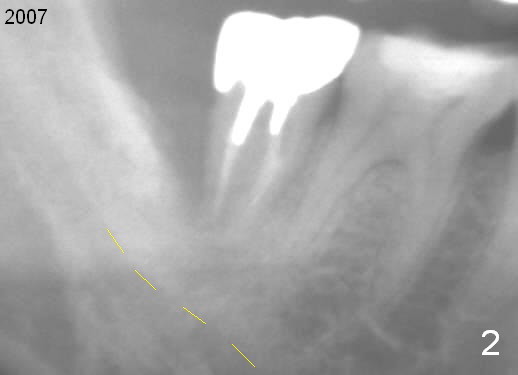

Complex Distal Defect

A 44-year-old man has had an asymptomatic distal defect of the tooth #31 for 8 years (Fig.1-5).  Recently there is an acute episode of swelling and pain.  A fistula develops mesiobucally.  Panoramic X-ray films tend to show that the distal defect is deep (Fig.2,5; yellow dashed line: upper border of the Inferior Alveolar Canal).  In addition, the distal defect may be not even buccolingually, as indicated by white and red arrowheads in Fig.3,4.  Following placement of a 6.9x10 mm bone-level implant, a 7.8x4 (4.5) mm cemented abutment is inserted for try in (Fig.6).  When it is fit, it is removed and a cover screw is temporarily placed.  A piece of Osteotape (~10x4 mm) is placed distobuccally or distolingually (depending upon which wall is lower).  A small amount of bone graft is packed between the most coronal portion of the implant and the Osteotape.  The cover screw is then removed and the abutment is re-inserted and tightened by hand.  An immediate provisional is fabricated with well-trimmed margin.  Reline is done if necessary for securely holding bone graft in place.  A new PA is to be taken prior to surgery to determine the extent of the lesion.  Photos are taken to show the mesiobuccal fistula.  Return to Lower Molar Immediate Implant Xin Wei, DDS, PhD, MS 1st edition 04/12/2015, last revision 05/25/2018